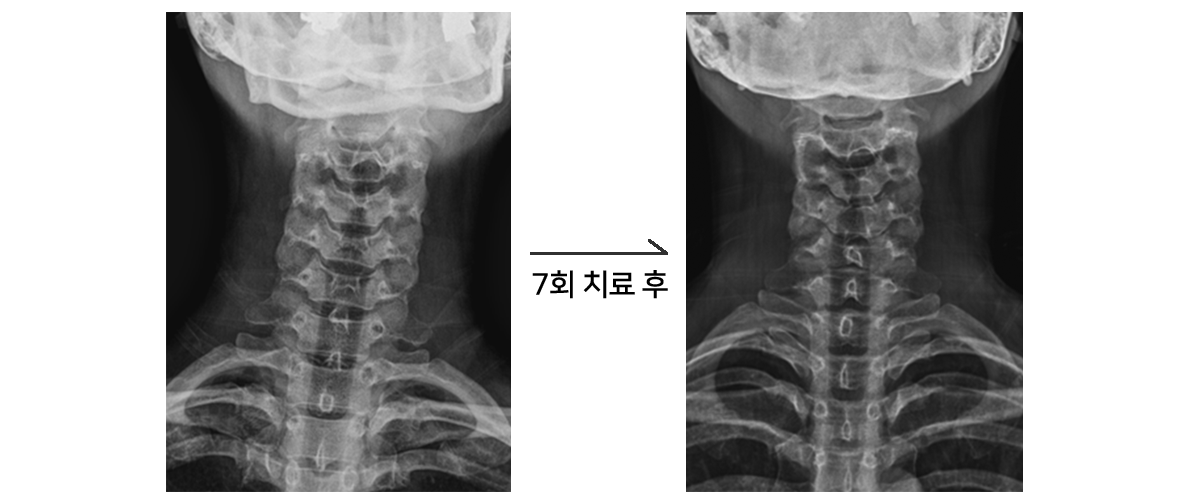

불균형 증후군으로 인한 틀어짐 교정

횟수 : 증상 호전 6~8회 , 교정 목적 25~30회